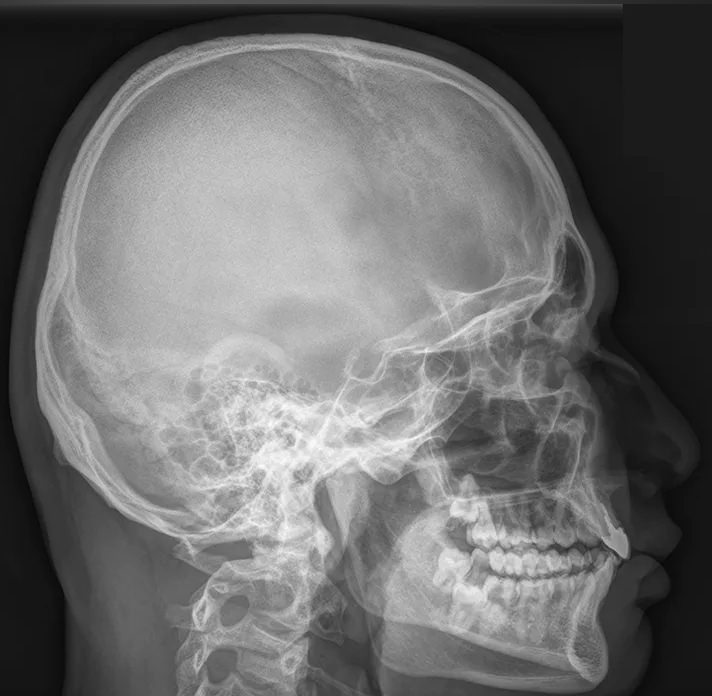

Череп устроен крайне сложно, так как содержит в себе множество важнейших органов: головной мозг и его кору, черепно-мозговые нервы, железы внутренней секреции, органы зрения, слуха и частично ― дыхательной и пищеварительной систем. Для каждого есть свой специфический участок с уникальным строением. Несмотря на то, что большинство этих органов относительно мягкие, они оказывают свое влияние на твердые кости черепа, оставляя на них следы при патологических изменениях. Поэтому рентген, как наиболее доступный и эффективный метод диагностики костной ткани, назначается одним из первых.

Снимки черепа требуют специального подхода во время рентгенодиагностики. Одно из основных требований ― соблюдение симметричности правой и левой стороны при фронтальной, то есть прямой рентгенографии. Также часто назначают снимок в боковой проекции, реже ― подбородочную, затылочную и прицельные снимки определенных костей.

В протоколе рентгенолог описывает следующие элементы:

• Кости, их форма, размеры, соотношение, видимость швов;

• Толщина костей в разных участках;

• Контуры внешние и внутренние;

• Следы «пальцевых вдавлений» и сосудистый рисунок;

• Состояние турецкого седла, его числовые значения;

• Наличие воздуха пазухах и их состояние;

• Переломы;

• Участки обызвествления;

• Новообразования.